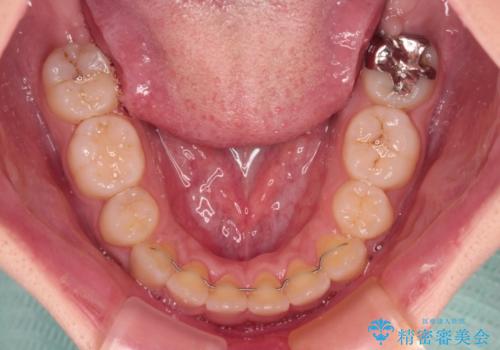

上顎歯列幅を拡大したことで、デコボコを容易に解消することができるようになったため、抜歯により得られたスペースを口元の突出感改善に利用することができました。